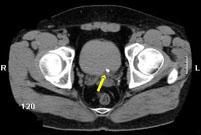

问题 男,29岁,反复发作血尿1年余,CT如图所示,下列说法正确的是 ( )

选项 A、左输尿管结石 B、膀胱结石 C、左侧输尿管扩张 D、左侧输尿管末端,膀胱入口处可见高密度影 E、左侧肾盂扩张积水

答案 ACDE